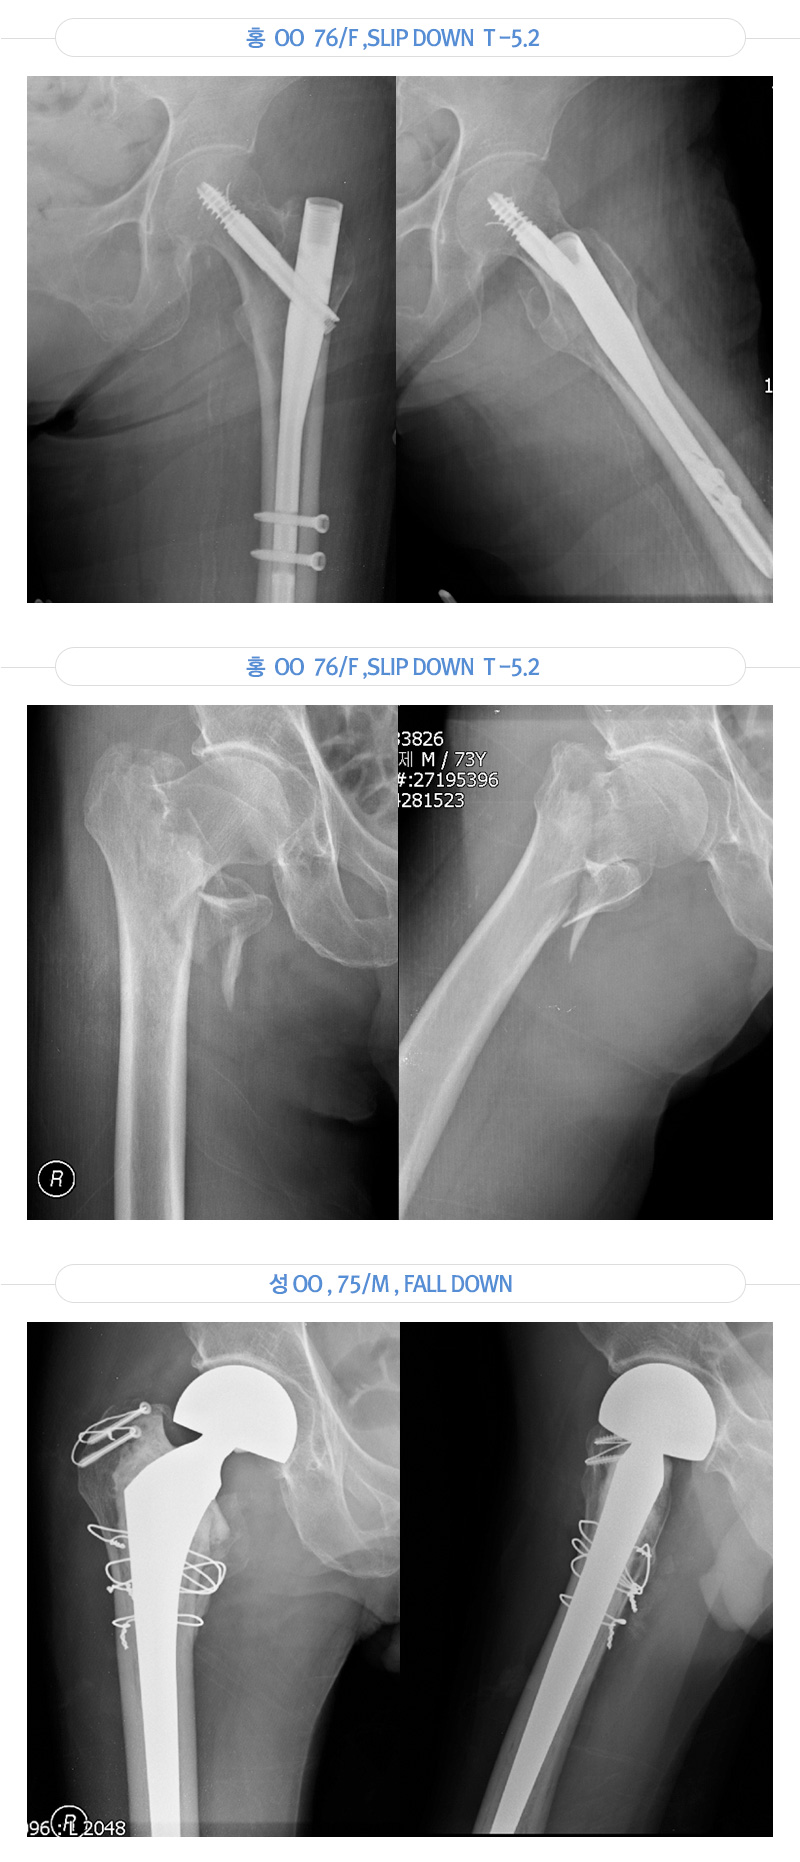

당뇨, 고혈압, 골다공증을 갖고 계신 어르신은 가벼운 충격에도 관절 주변 골절이 발생할 위험이 높습니다.

골다공증으로 인한 골절이 발생하면 정형외과, 내과, 마취통증의학과 등 관련된 여러 과의 협진하여 몸에는 무리가 되지 않는 국소 마취 및 수술을 진행하고 있습니다.

골다공증은 신체의 어느 뼈에서든지 일어날 수 있지만 골절이 일어나기 쉬운 부위는 주로 고관절, 척추, 손목이며 특별히 문제가 되는 부위는 고관절과 척추이다.